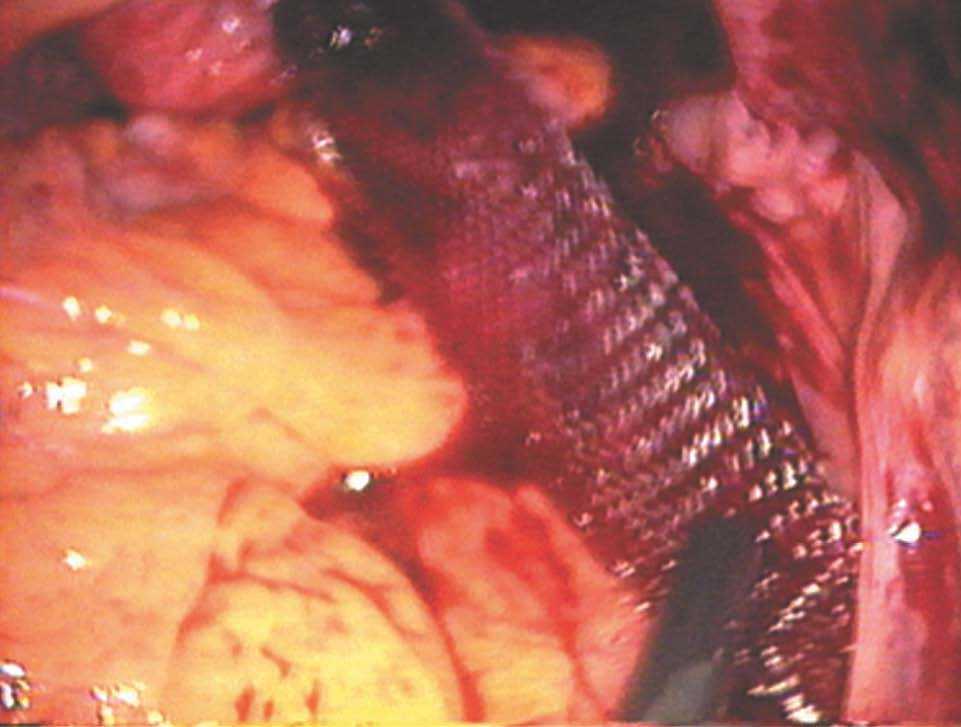

-- Paso sexto. Peritonización con una sutura continua para ocultar la malla. Visión final (figs. 20 y 21).

Figuras 20 y 21.Detalle de la peritonización de la malla.